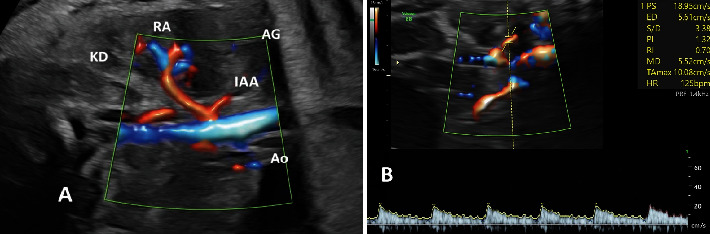

背景:生长受限(FGR)胎儿的子宫胎盘功能不全导致长期缺氧和应激,主要影响肾上腺。然而,其影响机制仍不清楚。研究目的本研究旨在比较 FGR 胎儿和发育正常胎儿的肾上腺动脉多普勒指数和肾上腺大小。材料和方法:于 2023 年 2 月至 12 月进行了一项多中心横断面研究。我们比较了 34 例 FGR 和 34 例发育正常婴儿的肾上腺下动脉(IAA)多普勒指数和肾上腺体积。结果显示FGR组的IAA峰值收缩速度(PSV)为14.9 ± 2.9 cm/s,而正常组为13.5 ± 2.0 cm/s,平均相差1.4 cm/s(95%置信区间[CI]:0.27-2.65;P值=0.017)。各组间的 IAA 脉动指数 (PI)、阻力指数 (RI) 或收缩/舒张 (S/D) 均无明显差异,P 值分别为 0.438、0.441 和 0.658。FGR组校正后的整个肾上腺体积和校正后的新皮质体积明显更大,P值分别为0.031和0.020。结论FGR胎儿的IAA PSV增加,校正后的整个肾上腺和新皮质体积增大,表明肾上腺对宫内慢性应激有明显的适应性。

Background: Uteroplacental insufficiency in fetuses with growth restriction (FGR) leads to chronic hypoxia and stress, predominantly affecting the adrenal glands. However, the mechanisms of impact remain unclear. Objectives: This study is aimed at comparing the Doppler indices of the adrenal artery and the adrenal gland sizes between FGR and those with normal growth. Materials and Methods: A multicenter, cross-sectional study was conducted from February to December 2023. We compared 34 FGR to 34 with normal growth in terms of inferior adrenal artery (IAA) Doppler indices and adrenal gland volumes. Results: The IAA peak systolic velocity (PSV) in the FGR group was 14.9 ± 2.9 cm/s compared to 13.5 ± 2.0 cm/s in the normal group, with a mean difference of 1.4 cm/s (95% confidence interval [CI]: 0.27-2.65; p value = 0.017). There were no significant differences between groups in terms of IAA pulsatility index (PI), resistance index (RI), or systolic/diastolic (S/D), with p values of 0.438, 0.441, and 0.658, respectively. The volumes of the corrected whole adrenal gland and the corrected neocortex were significantly larger in the FGR group, with p values of 0.031 and 0.020, respectively. Conclusion: Both increased IAA PSV and enlarged volumes of the corrected whole adrenal gland and neocortex were found in fetuses with FGR, suggesting significant adrenal gland adaptation in response to chronic intrauterine stress.